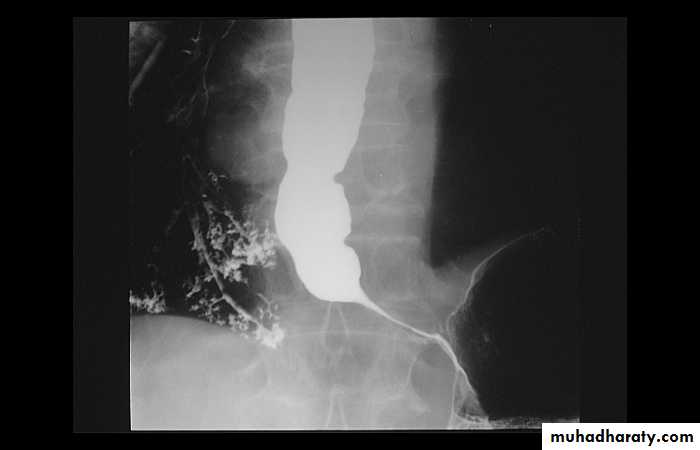

Annular Carcinoma

Narrowing :1-Constant.

2-Irrigular .

3-Variable length.

4- Shouldering sign.

5-Fistula (double tract).

6-Soft tissue shadow of the mass